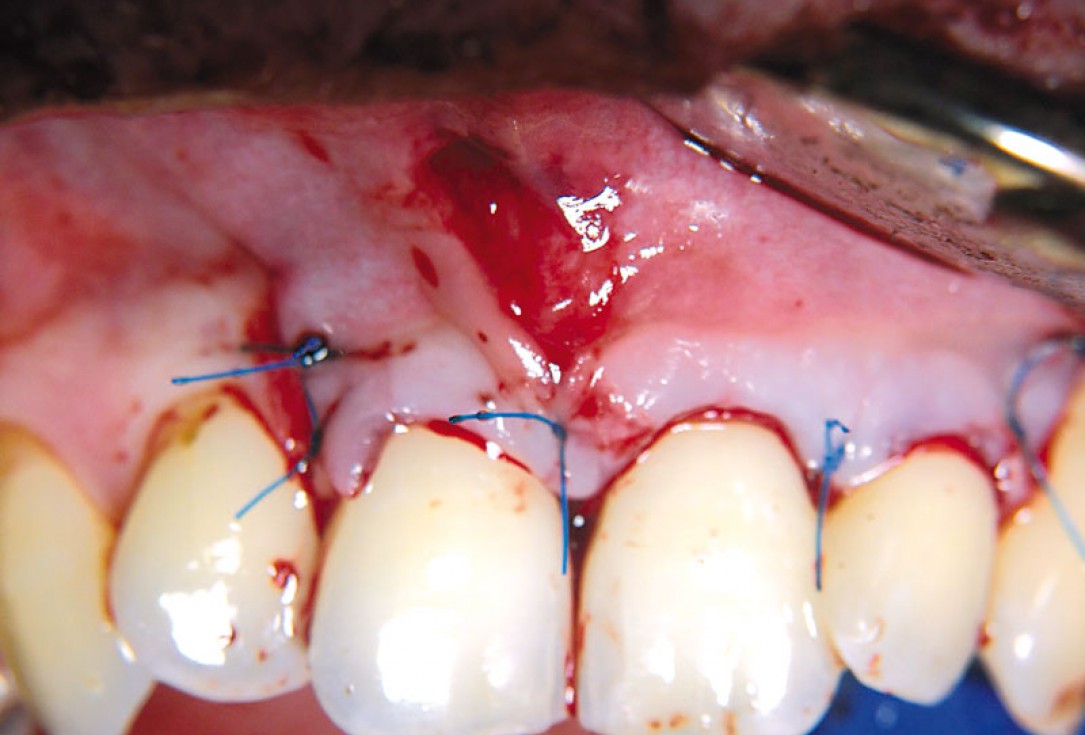

08/11 - Suturing of the membrane.Non-contained intrabony defect treated using cerabone®, collprotect® membrane and Straumann® Emdogain® - Dr. T. Schwaar (2)

09/11 - Flap closure.Non-contained intrabony defect treated using cerabone®, collprotect® membrane and Straumann® Emdogain® - Dr. T. Schwaar (2)